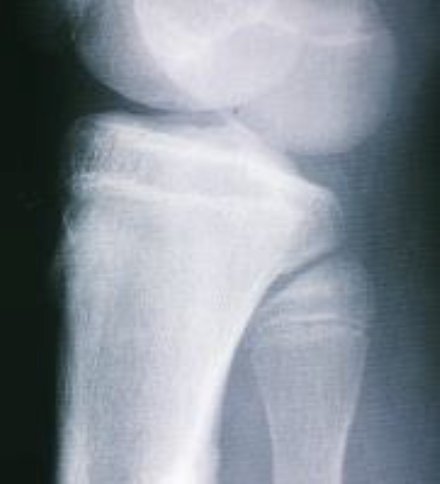

What is this view of the knee? Which views are missing?

AP

MISSING:

Lateral

Intercondylar

Skyline

Medial oblique